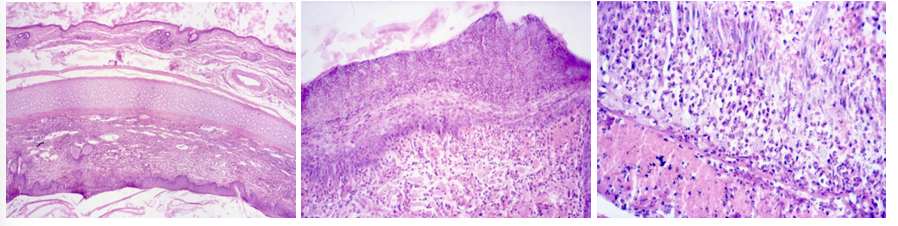

this is?

SCC (Canceroid- Squamous cell carcinoma)

Description: Cells resemble those of normal stratum spinosum, but have vesicular nuclei with one or more prominent nucleoli. We can observe eosinophilic stained formations growing into the dermis. Tumor cells spread throughout the dermis as slender anastomotic cords, with some cells falling off and remaining as isolated islands in the dermal stroma. Keratinization within islands results in laminated keratin pearls surrounded by tumor cells. At the periphery cells resemble basal cells following differentiated cells of stratum spinosum, and keratinization in the center.

Etiology: UV radiation (sunlight). Some breeds are more at risk than others.

Pathogenesis: Carcinomas are malignant epithelial neoplasms and SCC are tumors of squamous epithelium. They are common on eyelid and conjunctiva of cattle and horses, ear pinna of cats and sheep, vulva of cattle, goats and recently sheared sheep.